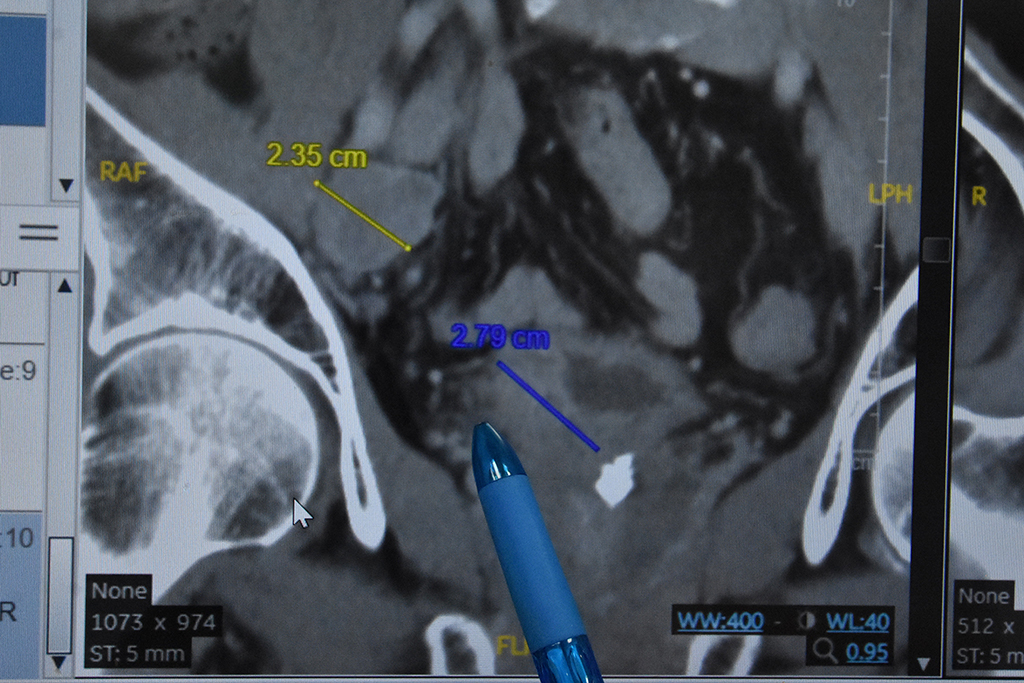

陳柏華醫師表示,詹先生2020年2月接受經「尿道膀胱腫瘤減積手術」,並在彰基檢測後確認符合健保給付免疫治療資格;2020年2到4月接受化療,同年6月開始每三個月給予免疫藥物治療,第一輪「免疫療法」後,影像及內視鏡切片都無殘留腫瘤,免疫療法結束18個月後,治療效果持續且無復發現象,近期僅需要持續追蹤即可。

陳柏華醫師表示,詹先生治療前的「尿路上皮癌」為第三期且有淋巴轉移,通常5年存活率約為30%。

陳柏華醫師表示,「免疫療法」結束18個月後,治療效果持續且無復發現象,近期僅需要持續追蹤即可。